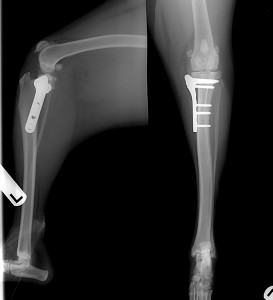

The TPLO neutralizes tibia motion by turning tibial thrust into tibial compression. During surgery, a cut is made in the tibia and the bone is then rotated. This produces a more level plateau that no longer allows thrust to occur. Since the tibial plateau angle varies between dogs, multiple x-rays of the knee are taken before surgery to determine the individual angle. After the cut is made in the bone and the plateau angle is leveled, a special bone plate is applied with screws to allow healing.

The TPLO technique allows for large dogs to have a 90% chance for returning to pre-injury function without arthritic development. If there is no ACL present, the thighbone or femur slips off the back of the shinbone forcing it forward as the dog walks (called cranial tibial thrust). TPLO surgery eliminates cranial tibial thrust by changing the angle of the top of the tibia (called the plateau). This prevents the femur from riding off the back of the tibia and forcing it forward.

With TPLO surgery, the pet has a quick recovery and usually becomes weight bearing within 2-weeks. The pet’s leg is bandaged and usually goes home after a two-night hospital stay. The healing process is approximately 8-weeks with strict rest and leash-only walks advised during this period.

At Vets & Pets, we re-evaluate the patient at 14-days, 4-weeks, 8-weeks, and 6 months postoperatively. During the 8-week and 6-month postoperative progress exam, the patient receives a full physical examination and the affected knee radiographed.